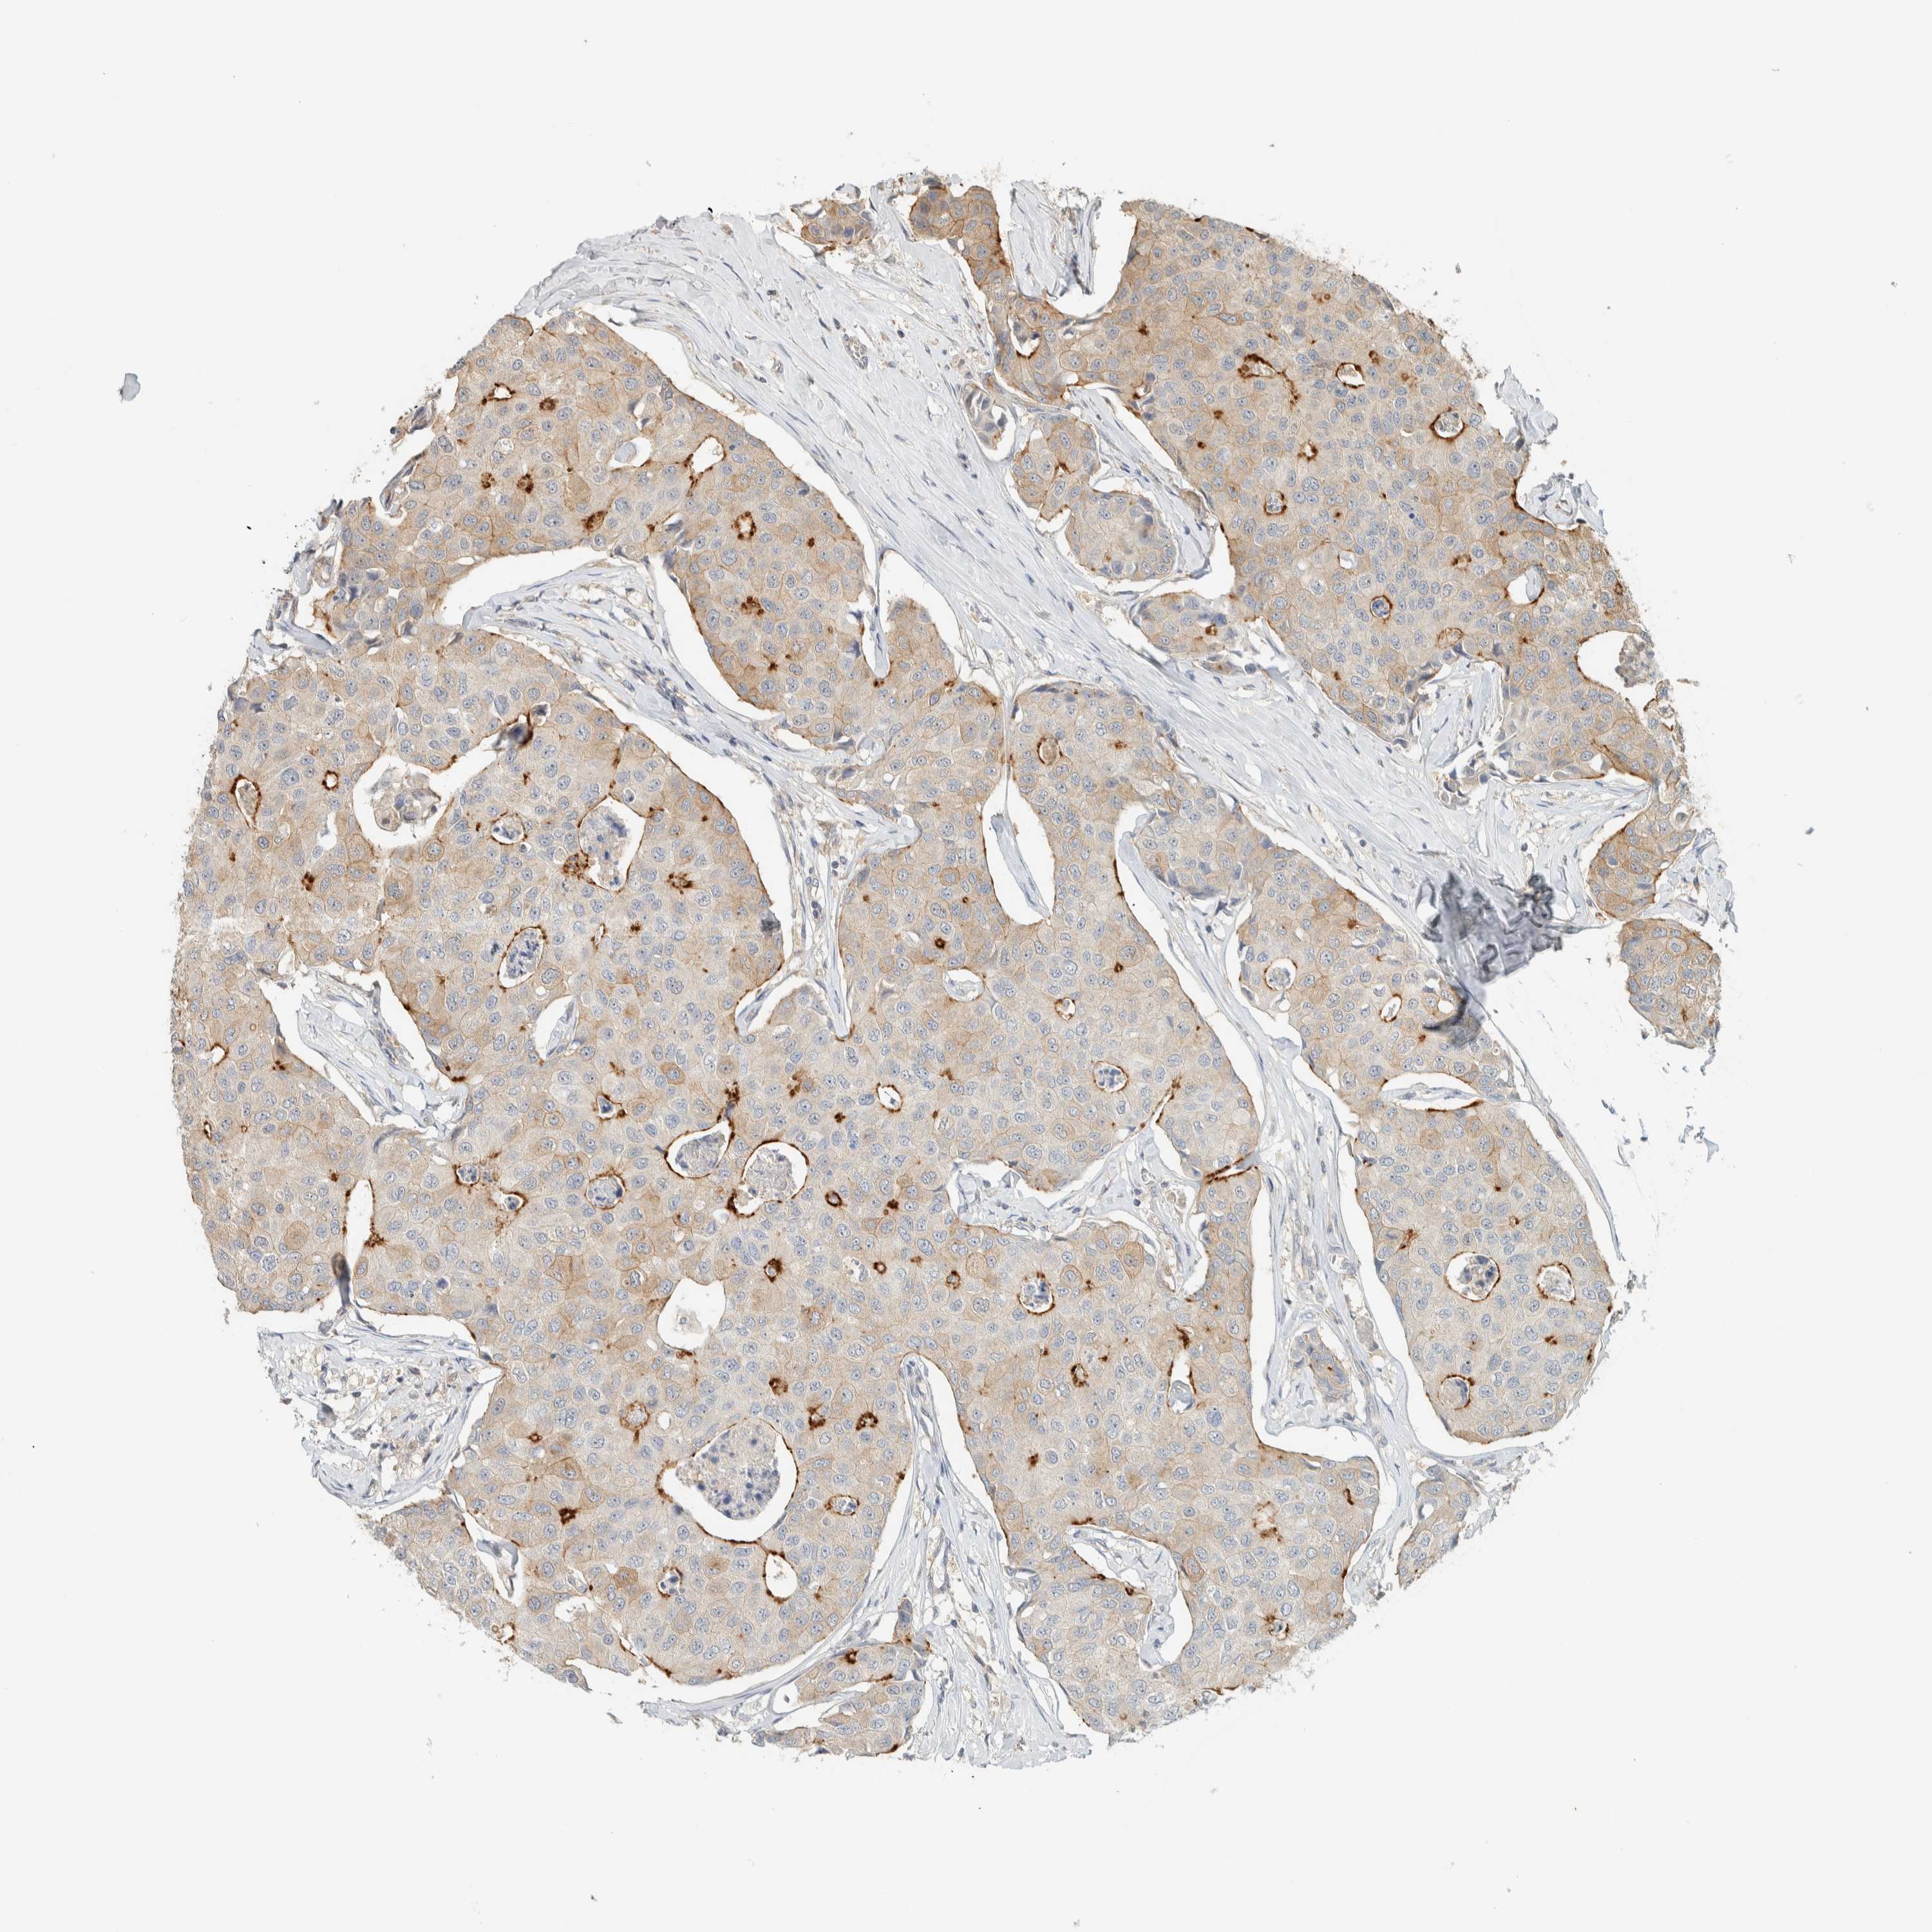

BRCA TCGA BRCA VALIDATION PROTEIN EXPRESSION